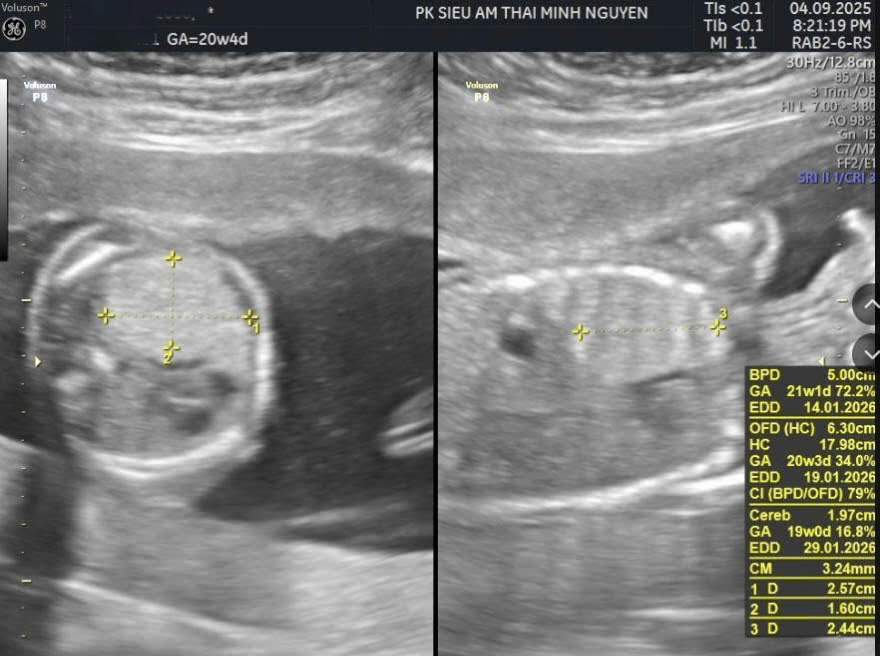

Chị L. đến phòng khám Dr Tú y học bào thai khi thai được 23 tuần 1 ngày. Chị mang theo sổ khám thai, kết quả siêu âm hình thái và một bản in kết luận từ cơ sở trước đó. Trên phiếu ghi: “Khối tăng âm phổi phải, nghi bệnh nang tuyến phổi bẩm sinh, trung thất lệch nhẹ”.

Trên siêu âm thai, bệnh nang tuyến phổi có thể biểu hiện bằng một nang lớn, nhiều nang nhỏ hoặc một khối tăng âm đồng nhất trong lồng ngực.

Bác sĩ sẽ đánh giá vị trí khối, kích thước, mức độ đẩy lệch trung thất và ảnh hưởng đến tim thai. Một yếu tố quan trọng là có hay không dấu hiệu phù thai.

Chỉ số CVR thường được sử dụng để ước tính nguy cơ biến chứng. Khi khối lớn nhanh hoặc CVR tăng cao, nguy cơ phù thai sẽ tăng theo.

Theo dõi định kỳ mỗi 2 đến 4 tuần giúp đánh giá xu hướng tăng hay giảm kích thước khối. Nhiều trường hợp có xu hướng ổn định hoặc giảm kích thước ở quý ba.